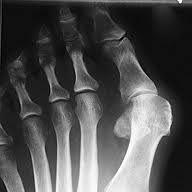

Hallux valgus før og etter operasjon.Hallux valgus er en feilstilling av stortåen (hallux) slik at den vris i retning lilletåen (valgus). Samtidig er stortåens grunnledd delvis ute av ledd og forskjøvet innover mot den andre foten. Typisk finner vi skjevhet i stortåen og sårhet over stortåens grunnledd. Leddet hovner opp og blir svært markert og prominerende på innsiden av foten, og det blir smertefullt og ømt. Forandringene i foten kan gjøre det vanskelig å finne sko som passer godt på foten.

- Tåen er deformert. Stortåen vinkles i økende grad i retning lilletåen.